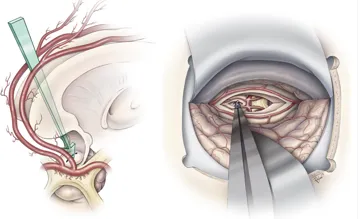

在顱咽管瘤術(shù)前考慮中,需要著重考量腫瘤的主要位置(交叉前、鞍后、交叉后),以及腫瘤與交叉、下丘腦附著的關(guān)系,垂體漏斗和垂體柄的位置,大而復(fù)雜的腫瘤可能需要聯(lián)合不同入路手術(shù)。

顱咽管瘤手術(shù)首要目標(biāo)是安全、徹底地到達(dá)并切除腫瘤;其次,要盡可能保留垂體柄。之所以要重點(diǎn)保護(hù)這兩者,是因?yàn)樗鼈儗?duì)于患兒未來的生活質(zhì)量極為重要。垂體柄涉及激素的分泌,下丘腦則像汽車的剎車和油門,負(fù)責(zé)調(diào)控激素分泌的節(jié)奏。

除此之外,手術(shù)還必須在不損傷視神經(jīng)等關(guān)鍵結(jié)構(gòu)的前提下,盡量實(shí)現(xiàn)腫瘤的全切除,防止復(fù)發(fā)。對(duì)于顱咽管瘤手術(shù)來說,保護(hù)垂體柄和視神經(jīng)功能的完整是主要的,如果能在這一前提下實(shí)現(xiàn)完全切除,則達(dá)到了理想的效果。